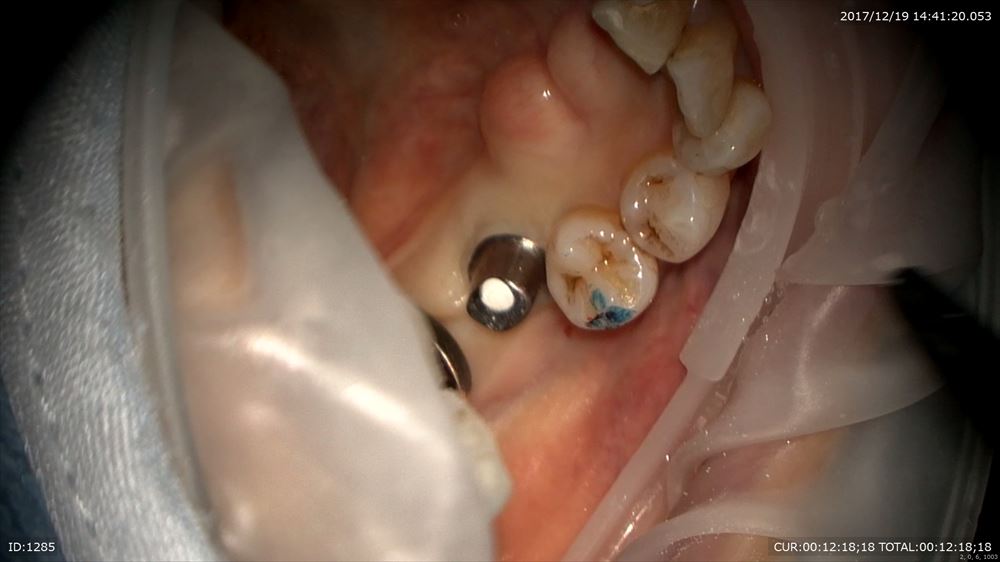

さて今日はマイクロスコープ治療での歯周病治療

若年性歯周炎

A.a菌による感染症が細菌検査で判明。こんなに歯石が。(16倍)

デブライドメント

無痛で綺麗に

レーザー